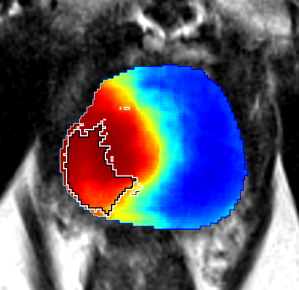

Qualitative Evaluation: Figure 4 shows the same slice as in Figure 2 with aligned T2W, ADC, and histopathology images, and prediction results using current state-of-the-art method [4], our CorrSigNet() and CorrSigNet(T2W, ADC, ) models. It may be noted that [4] fails to detect the cancerous regions on the left and right of the images, while the CorrNet representations alone can identify the cancer regions, and when combined with T2W and ADC images, they predict the cancer regions with high probability. It may also be noted that CorrSigNet(T2W, ADC, ) shows fewer false positives than [4]. This example shows the strength of learning correlated MRI signatures in identifying subtle, and sometimes MRI-invisible cancers. Figure 5 shows more example slices from different patients, comparing the state-of-the-art approach [4] and our prediction results with CorrSigNet(T2W, ADC, ). We note that our model with correlated features (1) can identify subtle and smaller cancer regions, (2) have better overlap with ground truth cancer labels, and (3) have fewer false positives.